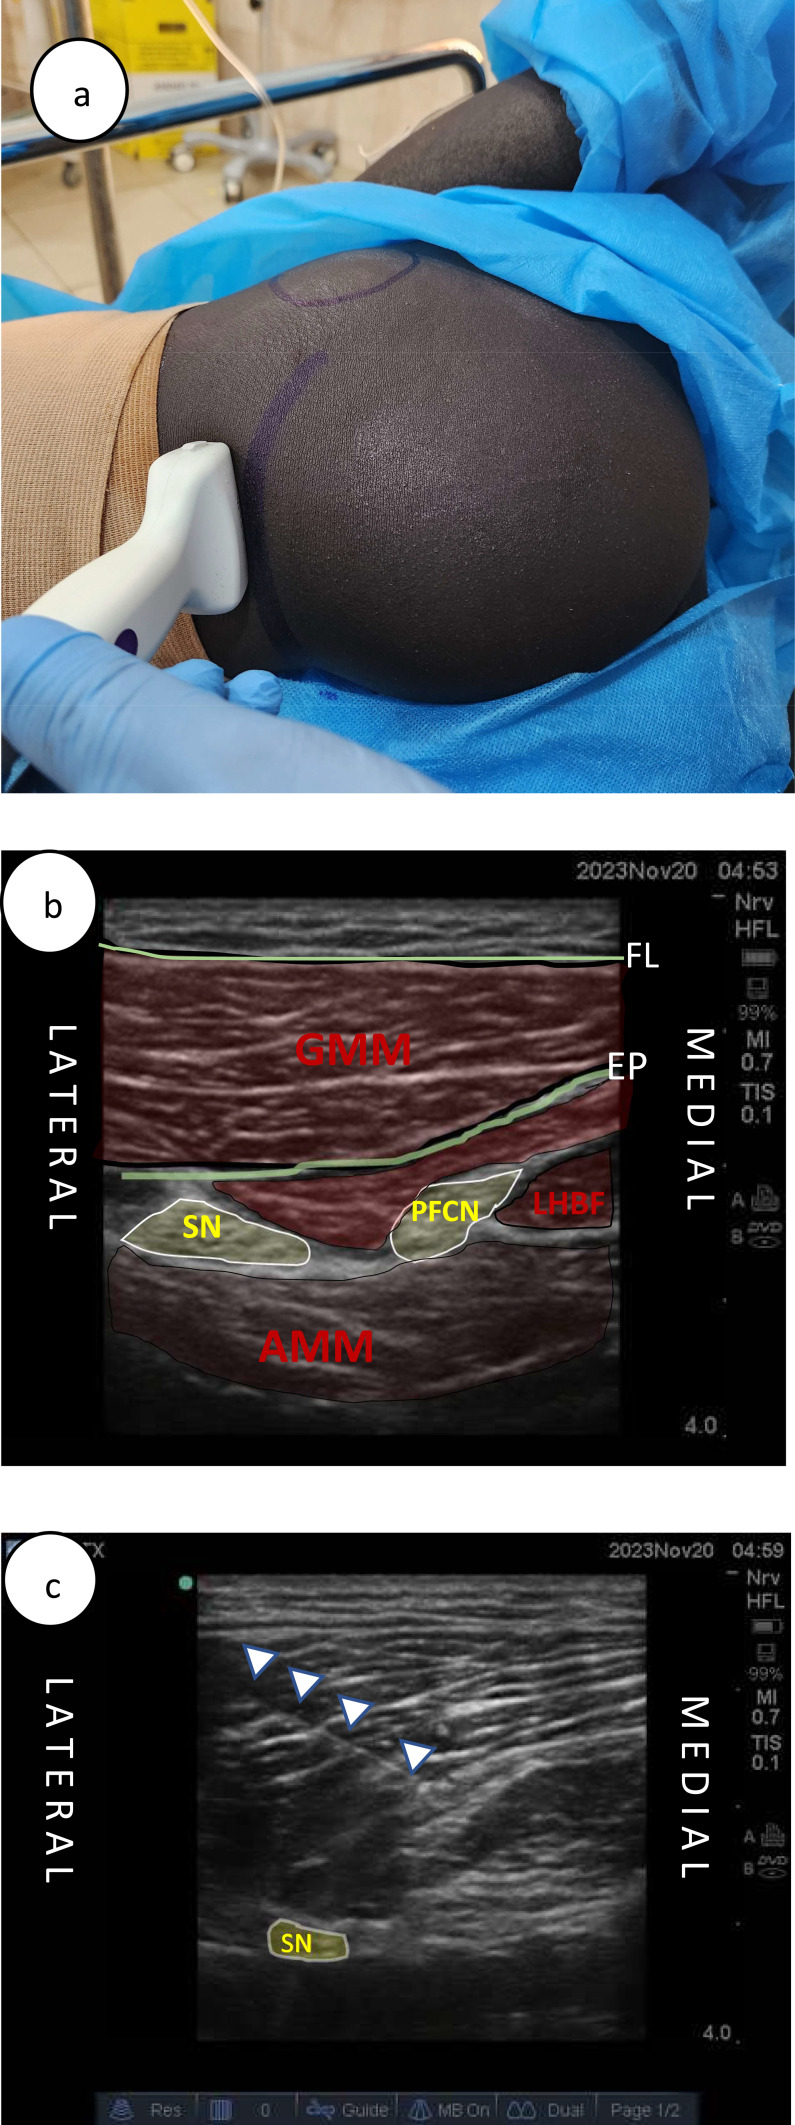

Purpose: The management of unstable patients with weapon-wounded lower limb vascular injuries presents significant anesthetic challenges. Regional anesthesia blocks, which combine lumbar and sacral plexus blocks, or their respective branches, minimize systemic effects and are deemed appropriate for high-risk patients requiring lower limb surgery. This case series aims to share our preliminary experiences with a combined anesthetic technique-sciatic nerve (SN), posterior femoral cutaneous nerve (PFCN), and supra-inguinal fascia iliaca (SIFI) blocks -in patients sustaining weapon wounds and undergoing lower limb vascular injury repair in austere environments.

Patients and methods: Seven patients with lower limb vascular injuries resulting from weapons who required surgery at district hospitals supported by the International Committee of the Red Cross were included in this study. Included patients underwent surgery for vascular repair and debridement using a combined nerve block technique involving the SN, PFCN, and SIFI blocks between May and December 2023. The blocks were administered using a 1:1 mixture of 1% lidocaine and 0.5% levobupivacaine.

Results: The combined block technique for the Sciatic Nerve (SN), Posterior Femoral Cutaneous Nerve (PFCN), and the Supra-Inguinal Fascia Iliaca (SIFI) were performed without complications in all patients. Three of the patients received light sedation prior to the initiation of the block procedure. All surgeries were completed successfully without the need for additional analgesics or conversion to general anesthesia.

Conclusion: The combined block technique for the Sciatic Nerve (SN), Posterior Femoral Cutaneous Nerve (PFCN), and the Supra-Inguinal Fascia Iliaca (SIFI) appears to be a safe anesthetic option for unstable or high-risk patients requiring lower limb surgery. Further research with a larger cohort is necessary to validate our findings and to potentially standardize this approach.